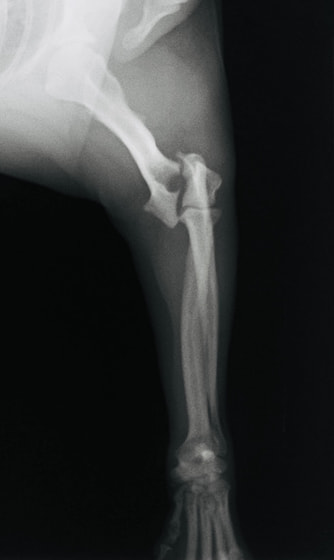

症例3:キルシュナーワイヤーのピンニングによる整復

ペルシャ猫 11ヶ月齢 雄

他院にて左大腿骨遠位の成長板骨折(salter-harrisⅠ型)が認められており、治療相談を目的として来院。当院にて、キルシュナーワイヤーを用いたピンニングにより骨折部位の整復を行いました。術後の経過は良好で、現在も経過観察中です。

術前レントゲン

術後レントゲン